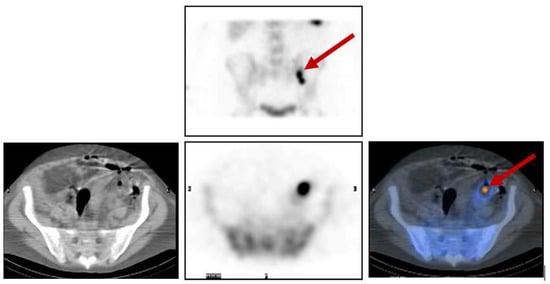

Figure 5 below illustrates the case of a 71-year-old female, known to have follicular thyroid carcinoma and skull bone metastases, after a total thyroidectomy with neck dissection and post-excision of the skull bone metastases. The patient was given a high dose of 5.5 GBq radioactive iodine (RAI) therapy, and the post-therapy scan shows iodine uptake in the neck, which is localised to the residual thyroid tissue on the SPECT/CT images, and iodine uptake in the left parietal bone, localising the residual tumour at the post-operative margins.

Figure 5.

(a) Anterior and posterior whole-body images of the post-therapy iodine scan showing iodine uptake in the neck and the left side of the skull. Physiological tracer distribution is seen in the salivary glands (as pointed out by the arrows), stomach, bowel loops, and urinary bladder. (b) CT and fused SPECT/CT images of the skull showing an osteolytic lesion with tracer uptake along the post-operative margin in the left parietal bone. (c) CT and fused SPECT/CT images of the neck clearly show tracer uptake in the residual tissue in the neck (seen as hot spots on the image on the right).